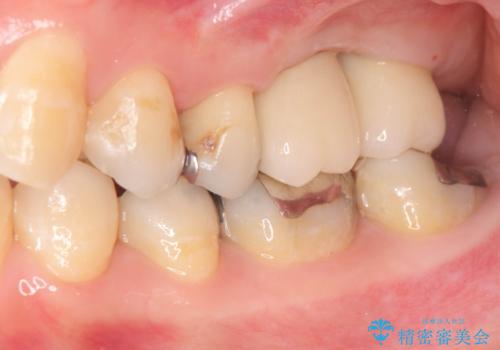

上顎奥歯のインプラント治療

- 奥歯を失い咬合機能の回復のためインプラント治療を希望され来院されました。

奥歯を2本失うと、他の歯の負担が増加し残っている歯の状態が悪くなるリスクがあります。

しっかりと咬合機能の回復できるインプラント治療を計画します。

- 88万円(インプラント×2・チタンカスタムアバットメント×2・ジルコニアクラウン×2・仮歯×2)費用は治療当時の料金となります

しっかりと食事ができるようになり、当院のインプラント治療に満足いただくことができました。